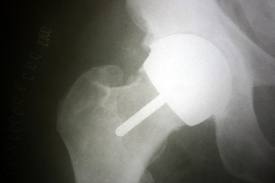

I am interested to learn whether the problem was caused by the BHR not being fitted at the correct angle which I understand is critical with this implant. If I were to post a picture of my X-ray of the BHR would anyone be able to tell whether indeed it was fitted at the correct angle?

My understand is that the ideal angle is 42 degrees but less than 50 seems OK for some.